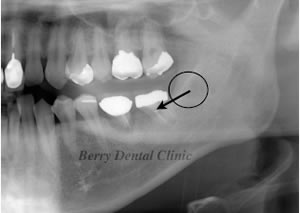

移植から2年後のお写真です。

矢印の部分に少し拒絶反応が認められますが、患者さんは痛くなく腫れもないので問題なく食事ができるという事でそのまま様子を見ています。